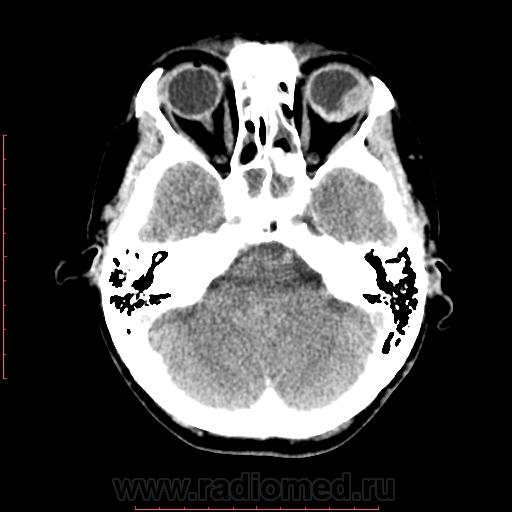

КТ орбит. Образование левого глазного яблока

Женщина 57 лет обратилась с жалобами на снижение зрения левого глаза. На УЗИ объемное образование левого глаза. Написал DDs меланома, ретинобластома.